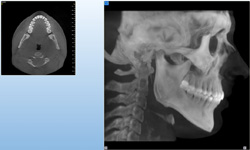

NewTom GiANO

Jedná se o nejnovějším přístroj ze skupiny dentálních hybridních CBCT (3D) + 2D (pan i ceph) systémů. Přístroj umožňuje na základě jediného snímkování vytvořit všechny typy RTG zobrazení, které jsou pro lékaře potřebné.

Používaná technologii tzv. „kuželového paprsku“ a speciální senzory pro minimální zátěž při snímkování pacienta

(o více jak 80% nižší dávka proti klasickému CT).

Pomocí tohoto přístroje je možné zjisti skutečnou situaci v čelistních kostech pacienta tedy množství kosti - můžeme změřit skutečnou šířku i výšku kosti, i kvalitu kosti (hustotu) v místě uvažované implantace. 3D (tříprostorové) zobrazení umožňuje

zvýšit prostorovou představu operatéra ještě před vlastní operací a zároveň pacientovi lépe objasnit a ukázat oblast plánovaného zavedení implantátu.

Pacient „neumí číst“ RTG snímky, ale díky 3D zobrazení vidí „svoji skutečnou čelist“ – např. jak je nízká či úzká, vidí průběh nervu nebo velikost čelistní dutiny, což mu umožní i pochopení nutnosti v některých případech provést pomocné zákroky

ještě před vlastním zavedením implantátu (více - Augmentace - kostní štěp, sinus lift, kostní granulát...).

Pomocí počítačových programů – NewTom Implant Planning a coDiagnostiX si lékař sám provádí veškerá potřebná zobrazení a měření.

Vyšetření pomocí tohoto přístroje a získaná data používáme

pro každou implantaci, dále ve stomatochirurgii (zlomeniny čelistí, zuby moudrosti, cysty, onemocnění čelistního kloubu), ortodoncii (retinované zuby, nadpočetné zuby), parodontologii atd.